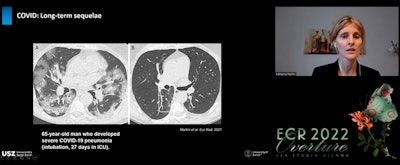

(A) CT shows a 65-year-old patient in subacute stage with bilateral ground-glass opacities and consolidation and in posterior lung area, signs resembling COP. (B) After six months, consolidation has mainly resolved but some ground-glass opacities remain in posterior right zone of lung and within this, an area of bronchial distortion.

(A) CT shows a 65-year-old patient in subacute stage with bilateral ground-glass opacities and consolidation and in posterior lung area, signs resembling COP. (B) After six months, consolidation has mainly resolved but some ground-glass opacities remain in posterior right zone of lung and within this, an area of bronchial distortion.Another interesting three-month finding on CT is mosaic attenuation pattern with areas of hypoattenuation in patients who had severe or critical disease, noted Martini. This mosaic attenuation can be best visualized in minimum intensity projection (MIP) and might be due to either microvascular obstruction or residual small airway disease.